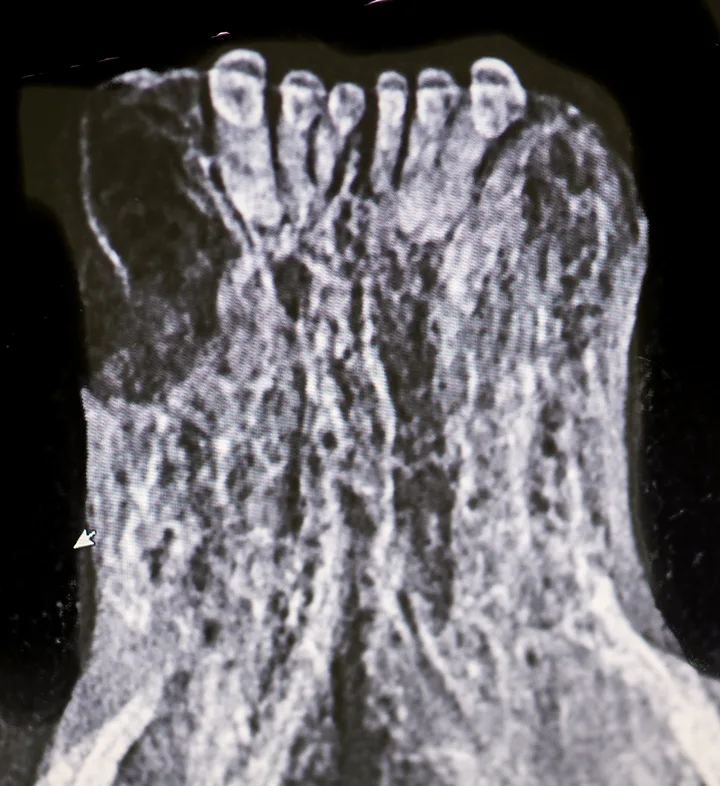

Surface resorption may occur secondary to release of osteoclast-activating factors at the site of cementum injury triggered by inflammation. Resorption can occur at any location on the root surface and progress into dentin apically and/or coronally. Surface root resorption (Figure 1) is radiographically characterized by one or more shallow voids that affect the cementum, which can extend into dentin located along the margins of the root. The periodontal ligament space and lamina dura may be locally affected.

Extracted third incisor from a cat with surface external root resorption extending to the oral cavity